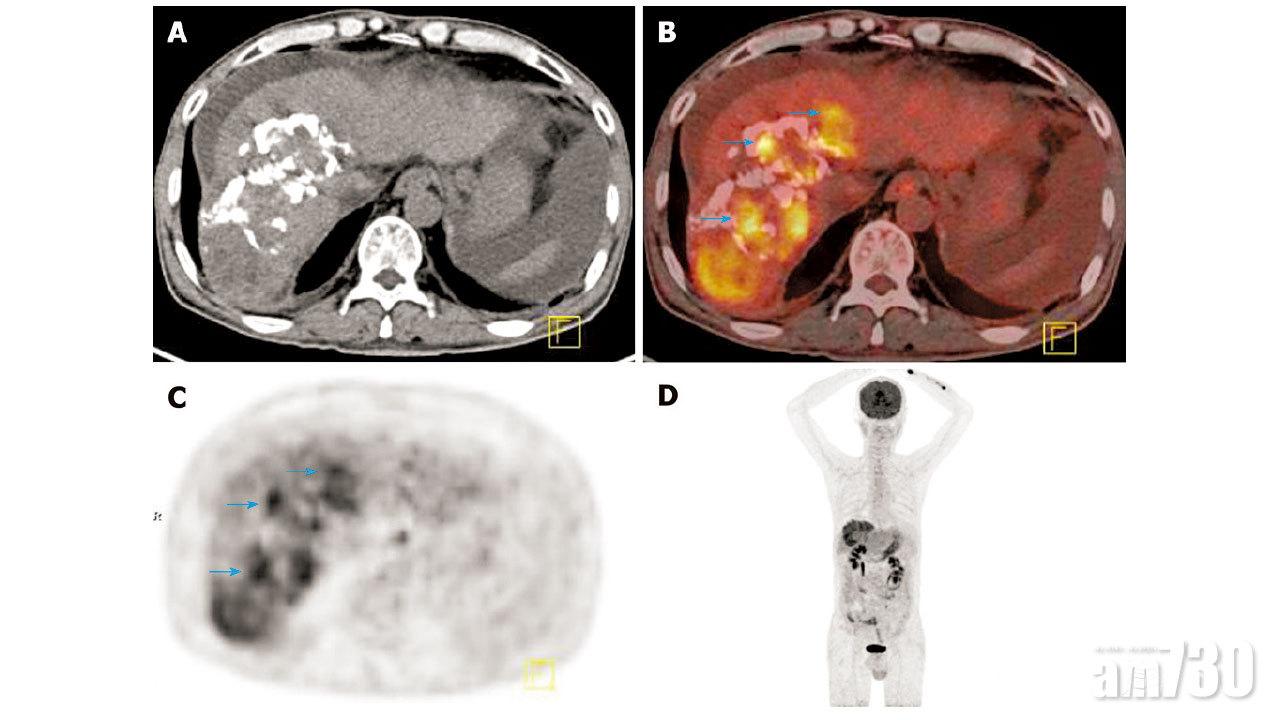

此外,還有一種可在香港使用的醫學影像技術──正電子電腦斷層雙融掃描(Dual-Tracer PET/CT)。這項技術可以準確地診斷肝癌,並確定肝癌細胞的擴散程度,然而檢查需時大約3小時,並涉及更高的輻射劑量,因此目前仍屬於二線檢查。鑑於病人的狀況各有不同,建議有需要的病人應先與醫生商討哪種是最適合自己的醫學檢查方式。